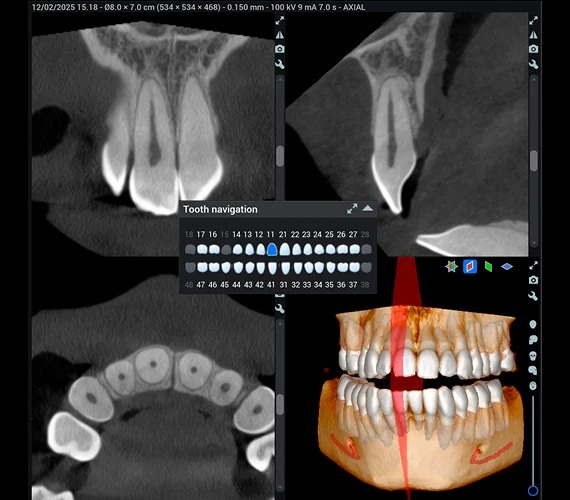

Navigace podle čísla zubu - Díky automatickému rozpoznání čísla zubu lze v CBCT objemu snadno navigovat pouhým kliknutím na číslo zubu v zubním diagramu – software automaticky zarovná všechny náhledy na vybraný zub. Kliknutím na číslo zubu lze také vyříznout konkrétní zub ze 3D zobrazení, což poskytuje vynikající pohled na jeho anatomii.

Nástroje pro endodoncii - Všechny naše 3D zobrazovací jednotky disponují speciálním vysokým rozlišením s velikostí voxelu 75 µm, které bylo navrženo přímo pro endodontické snímkování. V kombinaci s vynikajícími vizualizačními možnostmi softwaru Romexis je tento režim ideální pro endodontickou diagnostiku i edukaci pacienta. Lze snadno vyhodnotit kořenové kanálky, úrazy, zlomeniny kořenů i jejich resorpci – což umožňuje přesné stanovení diagnózy a plánování ošetření.

Výkonné diagnostické nástroje ve 3D - Univerzální diagnostické náhledy modulu Romexis 3D poskytují okamžitý přehled o anatomii pacienta – umožňují zobrazit snímky z různých projekcí nebo je automaticky převést na panoramatické snímky a řezy. Měřicí a značicí nástroje softwaru – jako je trasování nervového kanálu – dále podporují bezpečné a přesné plánování ošetření. Různé možnosti 3D zobrazení zlepšují vizualizaci a zároveň slouží jako skvělý nástroj pro edukaci pacientů.